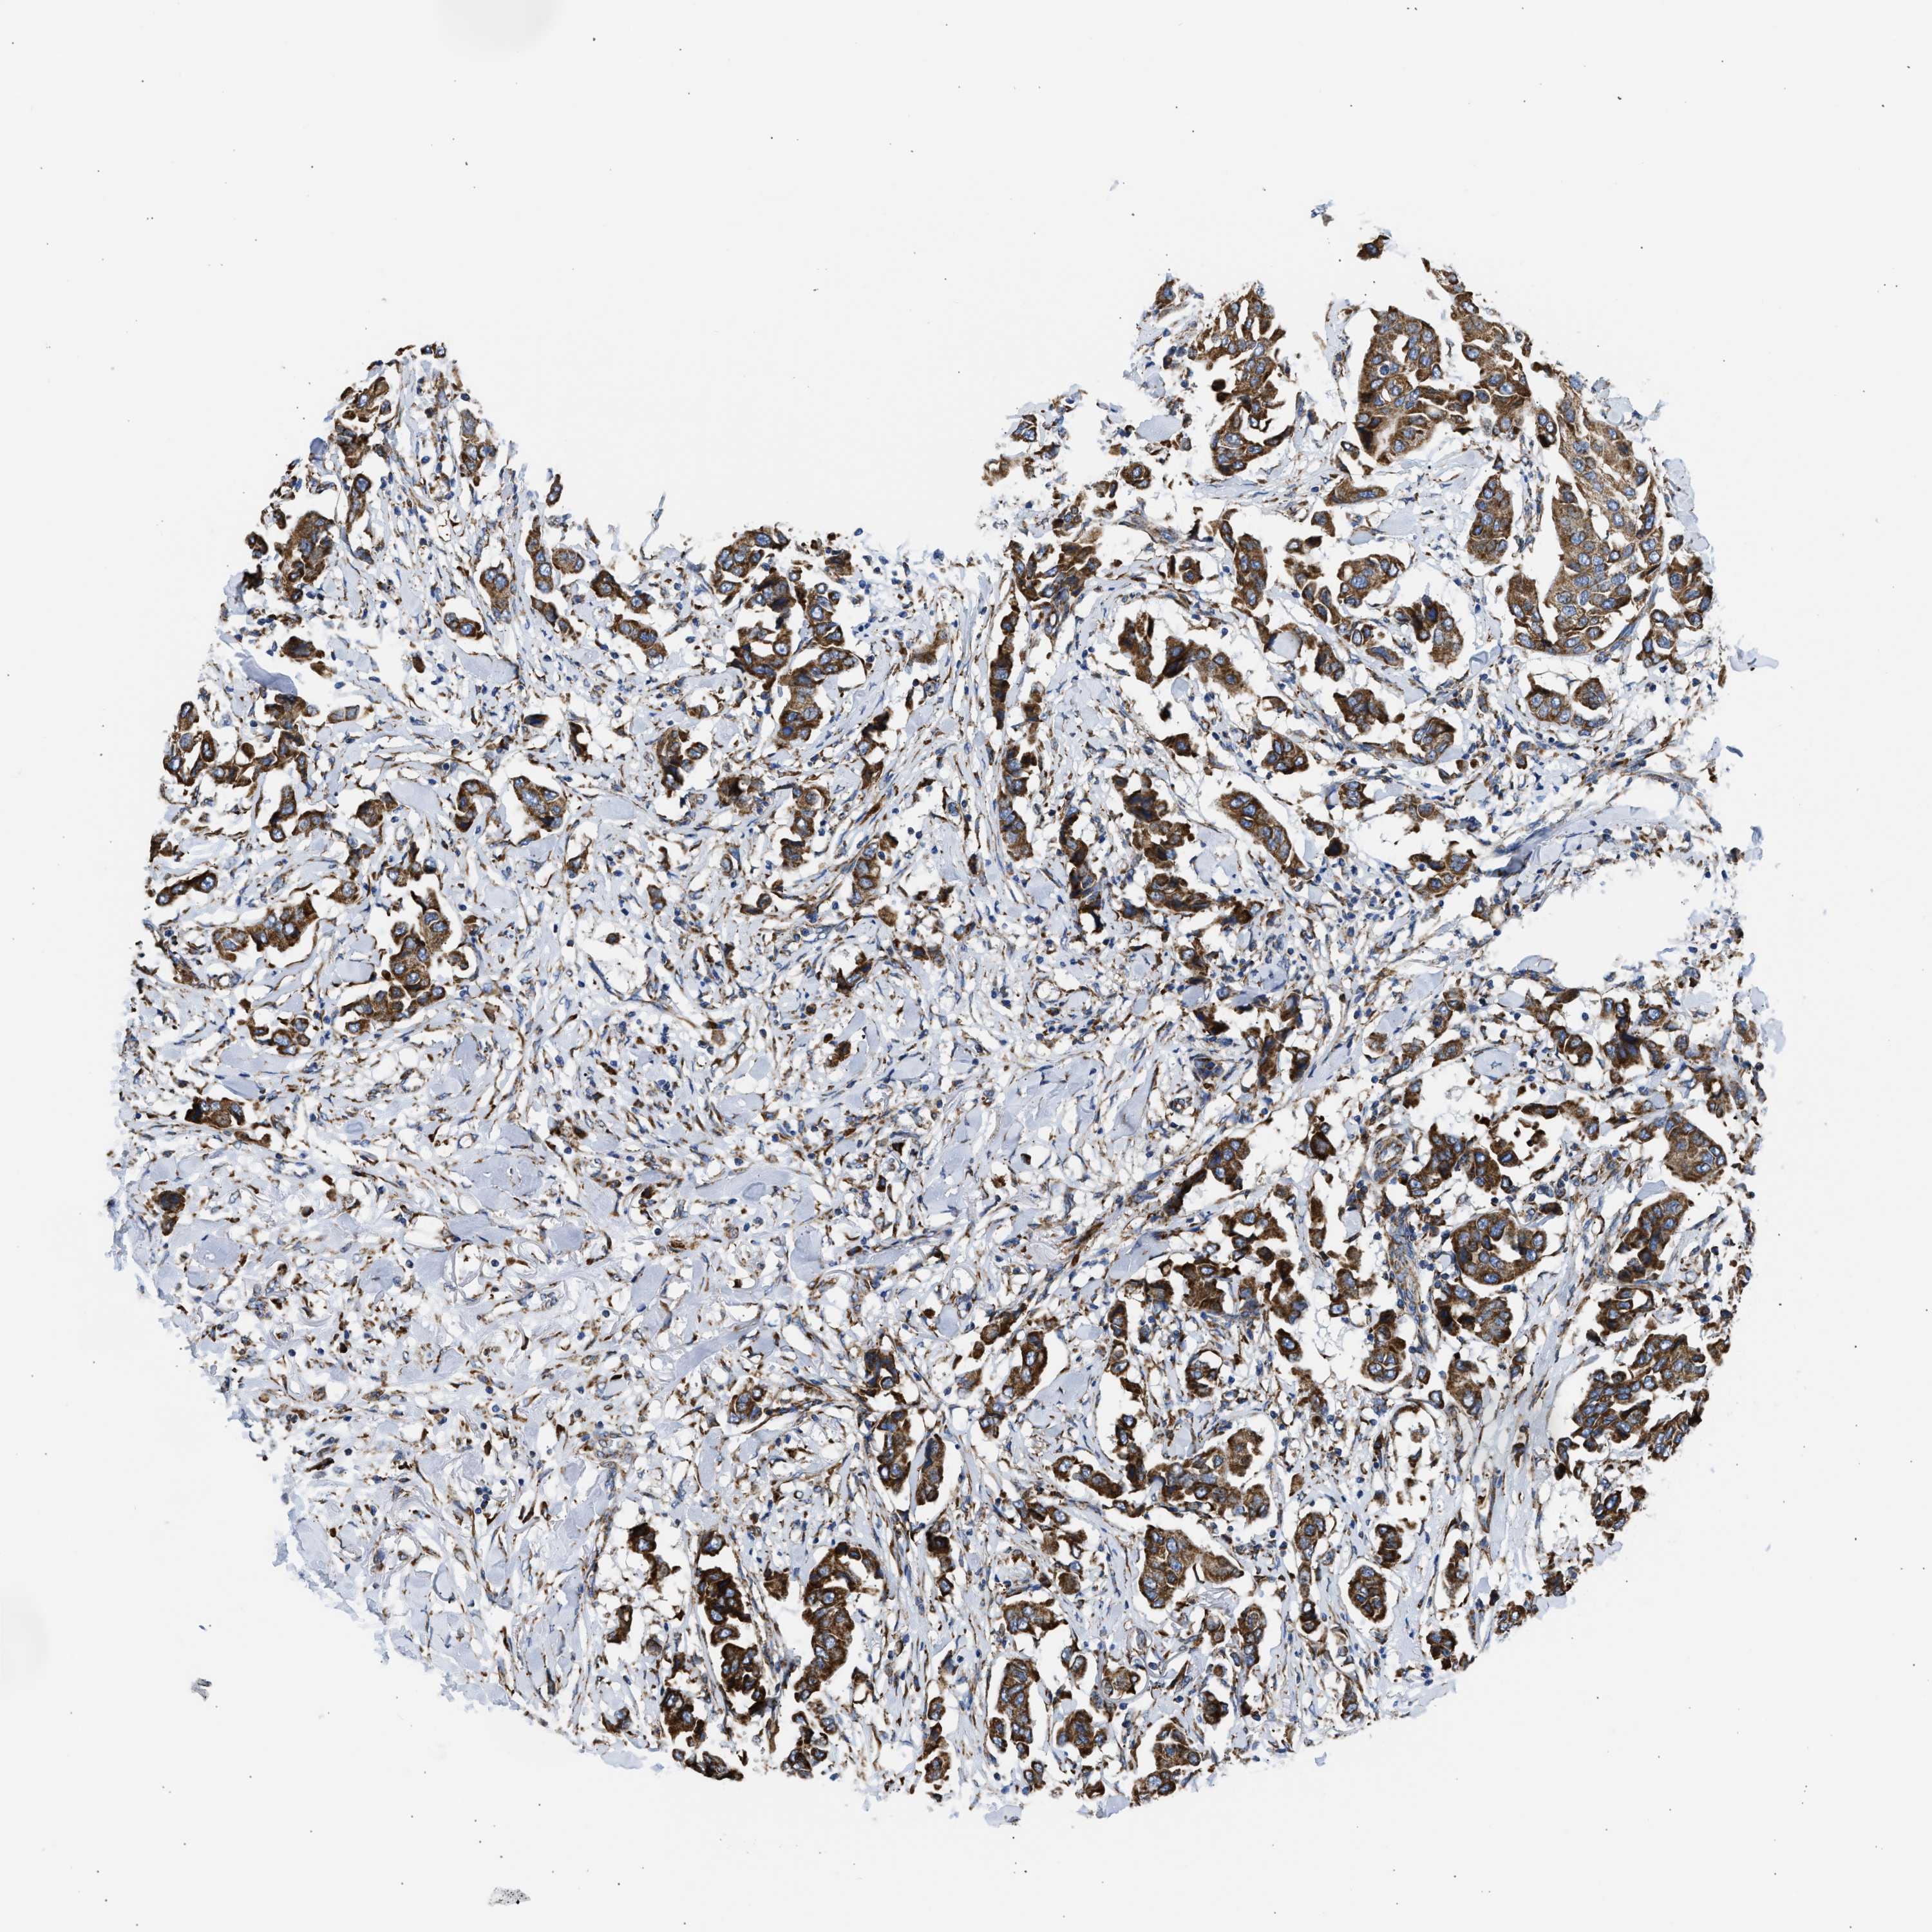

CANCER BREAST CANCER Show tissue menu

BRCA TCGA BRCA VALIDATION PROTEIN EXPRESSION